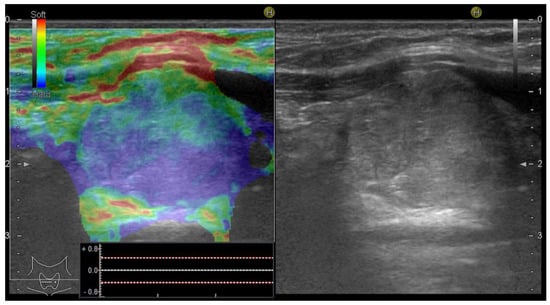

A risk upgrade was made in 14 cases with increased stiffness, defined as values of the SR above 3.9: an upgrade of the risk category from low to intermediate was made in 4 cases and medium to high risk in 10 cases (see Figure 6).

Figure 6.

Risk upgrade from intermediate risk in B-mode to high risk in B-mode + SE due to increased stiffness (Asteria 3). Pathology report confirmed PTC.